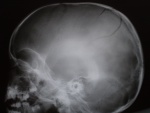

Какие будут мнения?

На представленной краниографии в боковой проекции определяется неполная линия перелома, распространяющаяся перпендикулярно сагиттальному шву, на обе теменные кости.

Заключение: неполный перелом теменных костей.